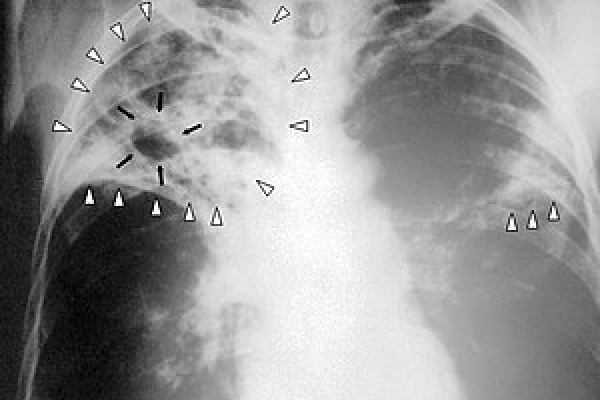

The company is on course to introduce Swaasa® X-ray in the pocket® & Swaasa® CT-scan in the pocket®. Salcit Technologies collaborates with the top academic and research institutions across the world such as AIIMS-Delhi, CMC-Vellore, Andhra Medical College-Visakhapatnam and University of California–San Francisco to test and validate its products and technologies. The results are published in the top scientific journals including Nature Scientific Reports.